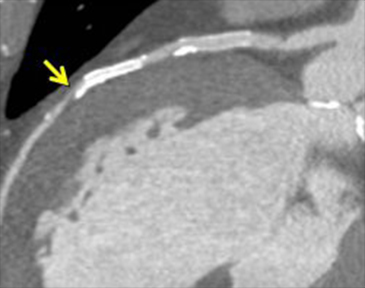

これにより冠動脈病変の部位と心筋虚血の関係をとらえ、適切な治療法の決定に役立てています。図4は労作性狭心症の症例です。ステントを留置した既往があり、最近になって再び狭心症症状が出てきました。左冠動脈前下行枝におけるステント留置部の遠位に狭窄病変がみられ、これが狭心症の原因となっている病変であることが分かります。

図4a 心臓CT